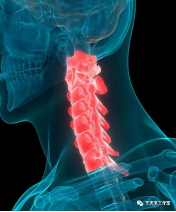

拯救颈椎病的“牵引”

拯救颈椎病的“牵引”拯救颈椎病的“牵引”颈椎病是指颈椎间盘组织退行性改变及其继发病理改变累及周围组织结构,出现颈肩部疼痛、上肢疼痛或麻木感、头痛头晕、恶心呕吐、行走不稳等临床表现,并出现相应的影像学改变。以40岁以上的中老年…查看详情+